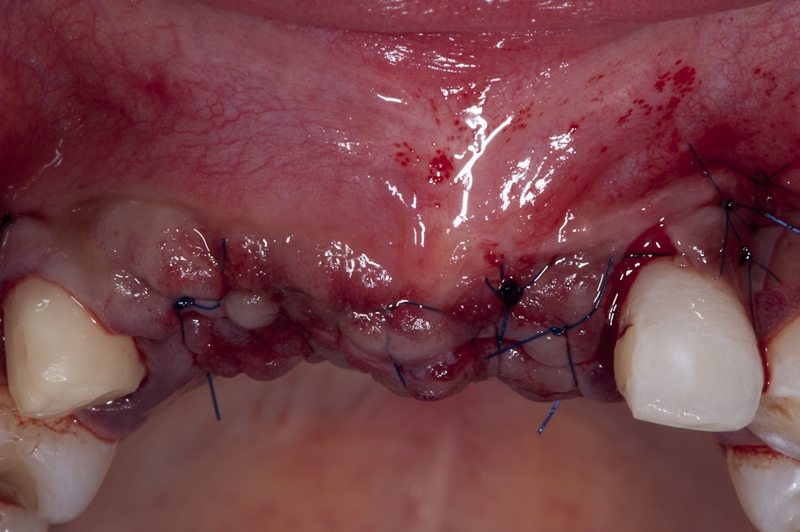

12/17 - Tension free flap closure with monofilament sutures

13/17 - Non resorbable sutures are stabilizing flap and sealing the wound